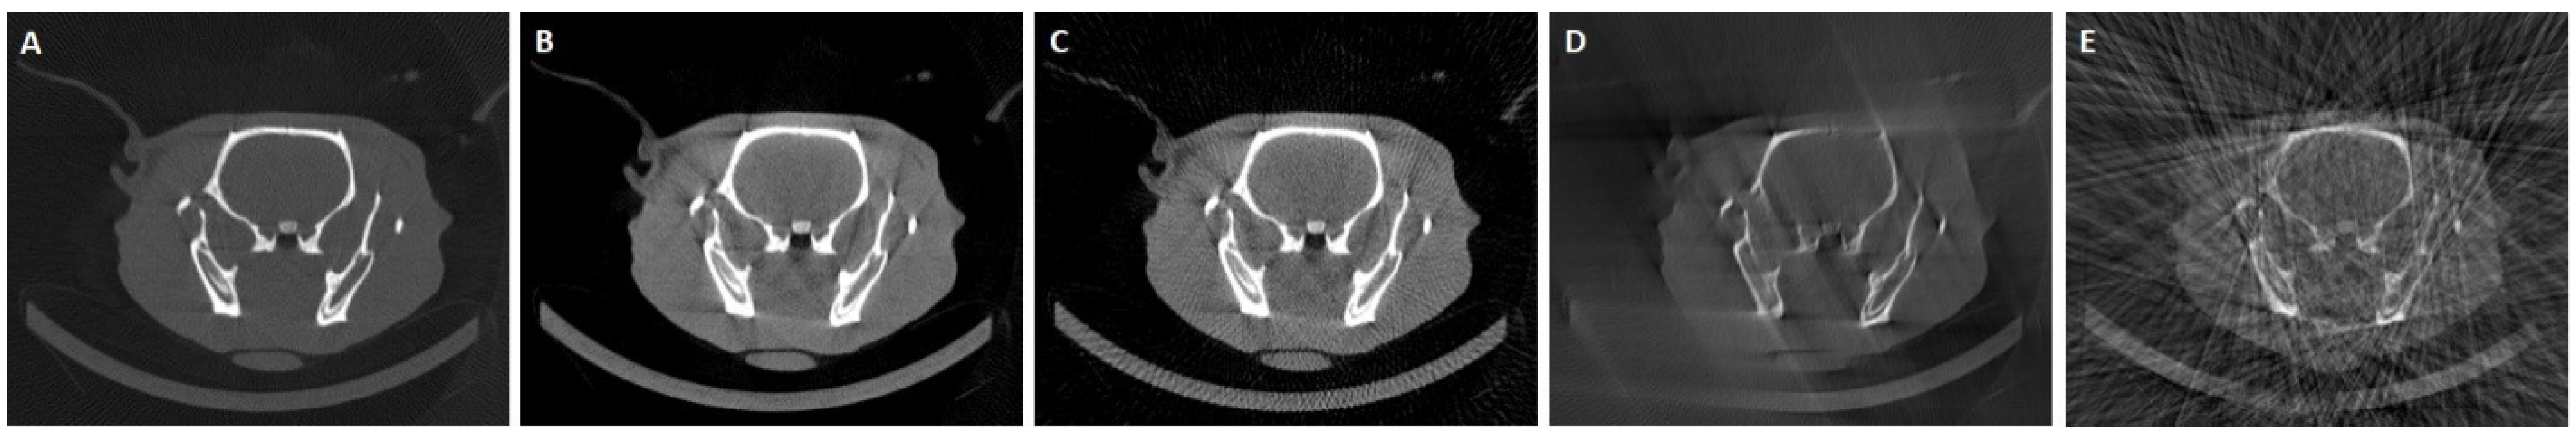

We trained and validated one model for each of the following four data scenarios generated from the acquired data of the 11 rodent studies (Figure 3):

Figure 3.

Central axial slice of the reconstructions of one of the tests cases for the target (A) and SD (B), LD (C), LSA (D), and LNP (E) scenarios.

- Standard dose (SD) scenario. Complete data, that is, 360 projections with a span angle of 360 degrees, resulting in seven studies for training, two for validation, and two for test.

- Low-dose (LD) scenario. We selected every second projection from each study (180 projections covering a 360-degree span), resulting in seven studies for training, two for validation, and two for test.

- Limited span angle (LSA) scenario. This scenario entailed the random selection of three span angles between 90 and 160 degrees for each of the 11 rodent studies. Consequently, we obtained a total of 21 studies for training, 6 for validation, and an additional 6 for testing.

- Limited number of random projections (LNP) scenario. We conducted three rounds of selection, randomly choosing a varying number of projections between 30 and 60 within a 360-degree span for each of the 11 datasets. This process yielded a total of 21 studies allocated for training, 6 for validation, and another 6 for testing.